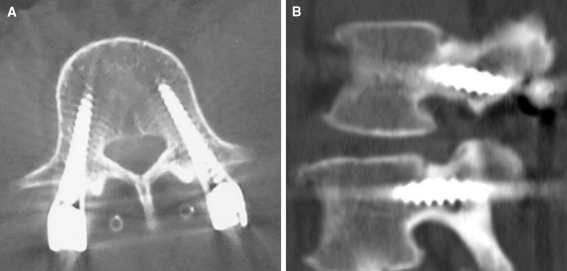

It is worthy to mention that the ideal position of the screw is achieved when the screw lies in the middle of the pedicle in both axial and sagittal reconstruction CT scans (Fig. 1)

Fig. 1.

Ideal position of the screw (a) axial (b) sagittal CT images